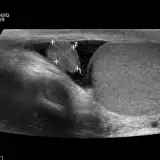

Over 2,100 interactive radiology cases, curated by radiologists for your level of training. Scroll, window, and view cases full screen โ€” just like on PACS. Click linked findings in each writeup to jump straight to them on the image. Cases include sample reports, a focused discussion section, original illustrations, and videos.

Casi completamente interattivi con gli strumenti che ti aspetti su un PACS: scroll, windowing, zoom, pan, misurazioni, ROI e modalitร  a schermo intero.

Annotazioni dettagliate evidenziano i reperti chiave direttamente sui casi. Clicca sui reperti collegati nella descrizione del caso per saltare alla loro esatta posizione sullo scan.